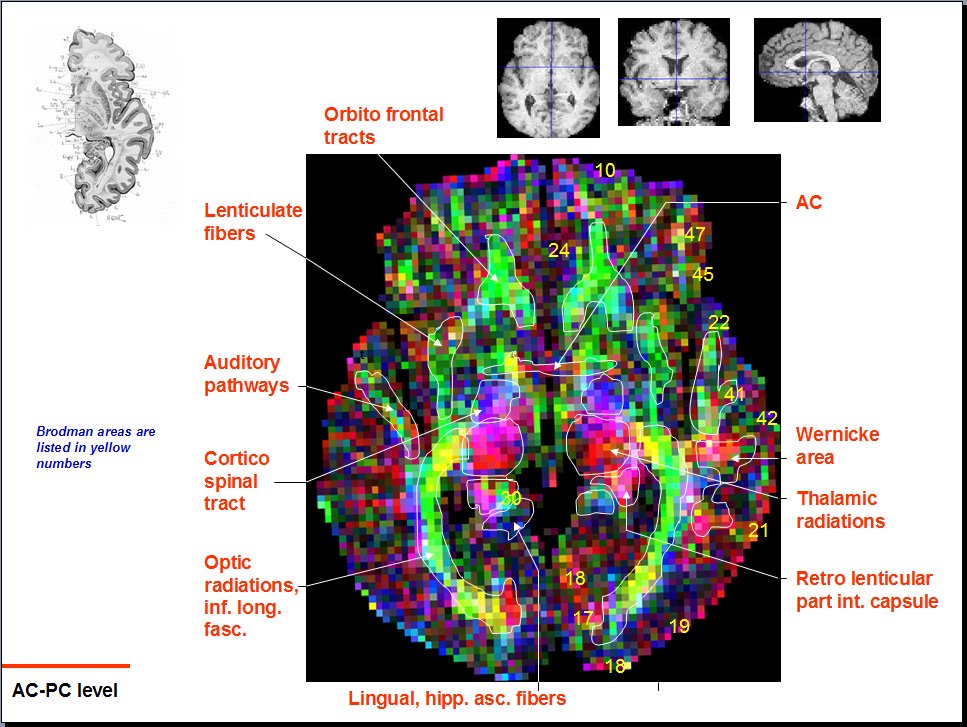

Diffusion Tensor Imaging: Neuroanatomy of Cerebral Hemispheres

Looking At: Neuroanatomy > Diffusion Tensor Imaging > Horizontal Atlas > Slide 18